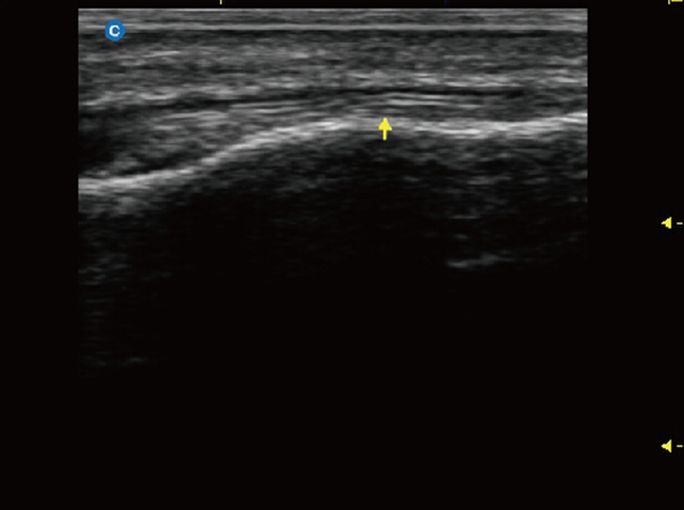

Узи сухожилий рук